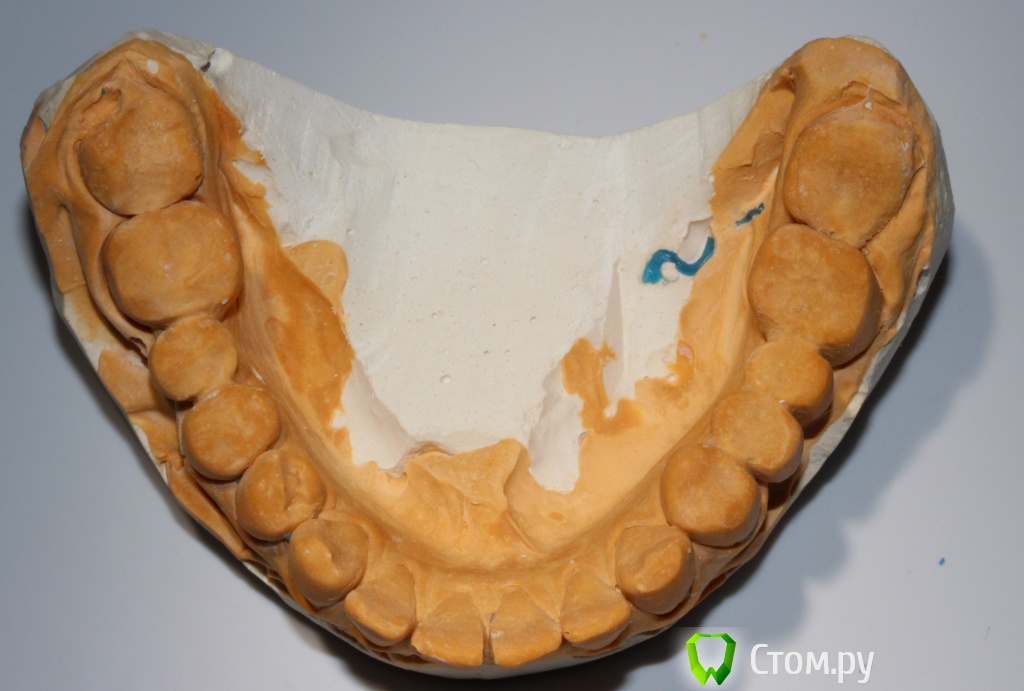

zzkz Опубликовано 6 марта, 2014 Поделиться Опубликовано 6 марта, 2014 Пациент 32 лет от роду. Известная особа в шоу бизнесе.С полостью рта не айс.Помогите разобраться и составить план лечения. Без лица(фото не делал) Жалобы на дискомфорт, трудность пережевывания пищи, с ее слов - как будто левая сторона не достает, в общем испытывает не удобства одни. На эстетику как ни странно ноль внимания. ВНЧС слева легкий щелчок при открывании/закрывании. Мышцы в норме. Но в фас и профиль подбородочная складка довольна выражена, как характерно при 2-ом классе. Фото моделей и панорама прилагаю Мой план пока таков:1. удаление 2-х восьмерок на н\ч2. каппа прозрачная, чтобы проверить реакцию ВНЧС при поднятии прикуса на пару месяцев3. снятие коронок4. воск5. импланты с аугментацией6. временное на металлопластмассе на имеющихся зубах7. через 4-5 мес. постоянные на имплантах как бы сделали Вы? Ссылка на комментарий

Ayrat_zub Опубликовано 7 марта, 2014 Поделиться Опубликовано 7 марта, 2014 апрайт 16,26? дистализация 37?(если это удасться) А что ей даст полноценная ортодонтия(инвизилайн или инкогнито)? Привести все в 1й класс? Как думаете если определить ЦС и от первых премоляров и дистальнее немного поднять прикус? Без большой ортодонтии. а так сказать полутотальчик, без фронтау вас фронт компенсировался под нынешнюю высоту, выровняв молряы получите открытый прикус во фронте, с протрузией нижних резцов, нужно полноценно работать тут, для максимально функционально-эстетичного результата. Сделайте сет ап, пациентке нагляднее будет. Из телевизора она или нет, результат одинаково нужен) сделайте ТРГ, самому станет понятнее) Ссылка на комментарий

Bobby Опубликовано 7 марта, 2014 Поделиться Опубликовано 7 марта, 2014 (изменено) Сначала узнайте готова ли она проходить лечение не менее двух лет, не нарушая при этом график лечения? Мой скромный опыт подсказывает, что личение публичных людей не столь сложно с медицинской точки зрения, сколь с организационный (частые отмены визитов, капризы, не своевременная оплата оказанных услуг). Касаемо клинической ситуации. В идеале провести ортодонтическое лечение, чтобы изменить овербайт и оверджет. Увеличение вертикального расстояния окклюзии (высоты прикуса) у пациентов со 2-м классом (дистальный прикус) всегда переносится хуже и в случае не создания на керамике ретрузионной защиты, может приводить к дискомфорту и даже дисфункциям жевательного органа. Реставративное лечение требуется только в боковых участках? Каково состояние передних зубов?Нужно ТРГ. Изменено 7 марта, 2014 пользователем Bobby Ссылка на комментарий